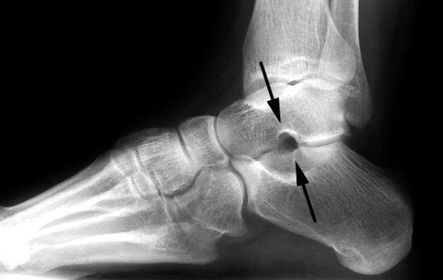

| What is this? What is shown by A and B? | STJ coalition A = talar neck spurring B = Halo or 'C' sign |

| What is this? | Posterior talocalcaneal coalition |